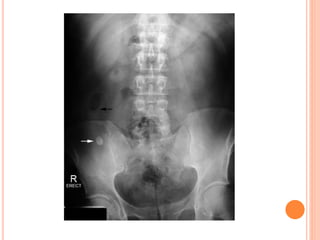

KUB

 Additional views:

- Oblique conventional

radiographs.

- Nephrotomogram.

- Open bladder film.

KUB ANALYSIS

 Musculoskeletal: evaluate all bone elements.

 Psoas muscle margin: straight, convex or absent.

 Intestinal gas: overlap, displaced.

 Kidneys

 Calcifications: overlying the UT or outside.

 Gas shadow: abnormal air at UT.